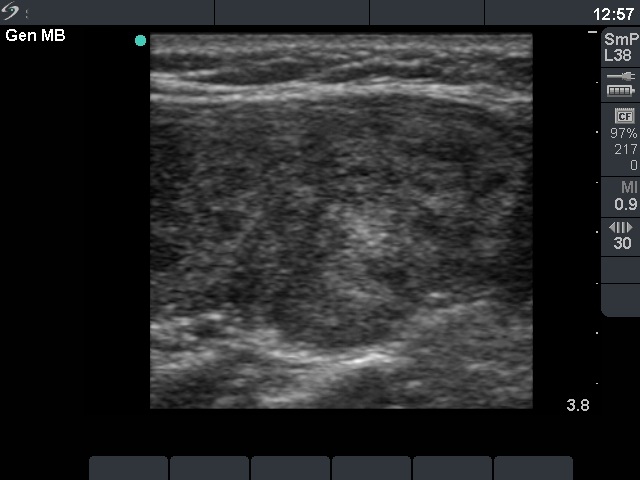

Ultrasonography: the thyroid was hypoechogenic with two well-circumscribed hyperechogenic areas in the right lobe. These were surrounded with a halo and presented perinodular blood flow.

Comment: it was unequivocal that the patient had Hashimoto's thyroiditis. The sonographic picture was equivocal whether the patient had nodule or nodules, too. However, the cytology was more problematic. It became evident after histopathology that the lesion in question was a focus with proliferation of oxyphilic cells. What did we do wrong? I think that such cytological picture itself is almost identical with that seen in a Hürthle-cell tumor. Although there were signs which disfavor the possibility of tumor, we could not exclude the presence of tumor with enough safety. Two minor signs were remarkable: firstly, the presence of nuclear debris which was suspicious for the presence of lymphocytic infiltration even within this lesion ; secondly, the lack of prominent nucleoli decreased the possibility of a Hürthle-cell tumor. The US appearance of the 'nodules' were remarkable. In contrast with a real nodule, these were irregular. Circumscribed areas were also found in the left lobe. Moreover, a follicular tumor is solitary in most cases.